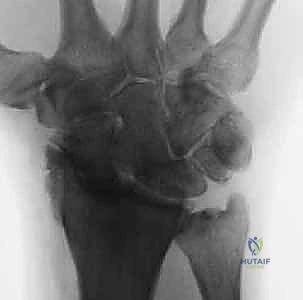

- Static Instability Signs (PA view):

- Increased Scapholunate Gap: A normal interval is less than 3 mm. Greater than 3 mm is the classic Terry Thomas sign.

- Scaphoid Ring Sign: The scaphoid collapses into flexion, causing its tuberosity to project in the coronal plane, appearing as a "ring."

- Volar Lip Overlap: The volar lip of the extended lunate may overlap with the capitate.

FIG 2 • A. PA radiograph demonstrating an increased scapholunate gap and a scaphoid ring sign. B. A fluoroscopic image of another example of an increased scapholunate gap. C. The contralateral wrist demonstrates a normal scapholunate interval.